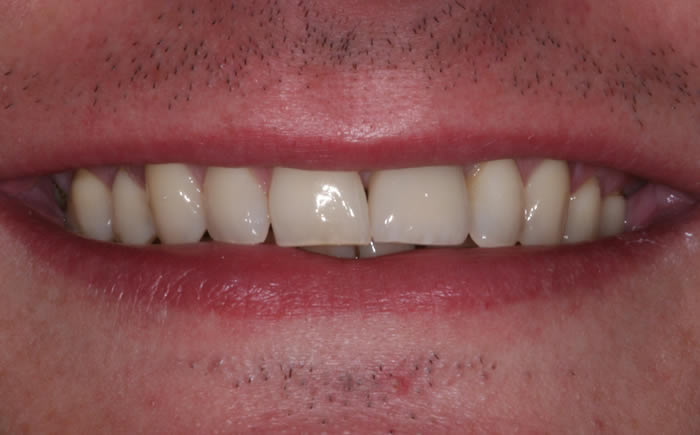

More front teeth replaced by dental implants

Case Three (4 images)